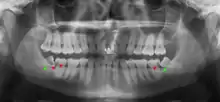

من المحتمل أن تنطمر ضروس العقل بسبب عدم التوافق بين حجم الأسنان وحجم الفك. تصنف ضروس العقل تبعًا لاتجاه انطمارها، وعمقها مقارنة بسطح العض للأسنان المجاورة وكمية تاج السن الذي يمتد خلال أنسجة اللثة أو العظم. يمكن أيضا تصنيف ضروس العقل تبعًا لوجود أو عدم وجود الأعراض والمرض. غالباً ما يبدأ فحص وجود ضروس العقل في أواخر مرحلة المراهقة عندما قد تصبح الأسنان المتطورة جزئياً منطمرة.يشمل الفحص عادة الفحص السريري بالإضافة إلى الأشعة السينية مثل أشعة البانوراما.

تصنف ضروس العقل تبعا لـ: اتجاه وعمق الانطمار، وكمية المساحة المتاحة لبزوغ الأسنان، وكمية الأنسجة الرخوة أو العظم (أو كليهما) التي تغطيها. تساعد بنية التصنيف الأطباء على تقدير مخاطر الإصابة بالالتهابات والعدوى والمضاعفات المرتبطة بإزالة ضرس العقل.[4] تصنف ضروس العقل أيضًا من خلال وجود (أو غياب) الأعراض والمرض.[5]

وجدت إحدى المراجعات أن 11٪ من ضروس العقل سيكون لها دليل على المرض ويجد لها [أعراض]، و 0.6٪ سيكون لديهم الأعراض لكن ليس لديهم مرض، و 51٪ سيكونون بدون أعراض لكن لديهم مرض حاضر، و 37٪ سيكونون بدون أعراض وليس لديها مرض.[5] غالبًا ما يتم وصف ضروس العقل المنطمرة من خلال اتجاه انحرافها (المائلة للأمام أو بزاوية إنسية هي الأكثر شيوعًا) وعمق الانحراف وعمر المريض بالإضافة إلى عوامل أخرى مثل العدوى الموجودة مسبقًا أو وجود الأمراض (الخراجات ، الأورام أو التهاب عظم الفكين).[3]:143–144يتم استخدام كل من هذه العوامل للتنبؤ بصعوبة (ومعدل المضاعفات) عند خلع الضرس المنطمر.[6][7]